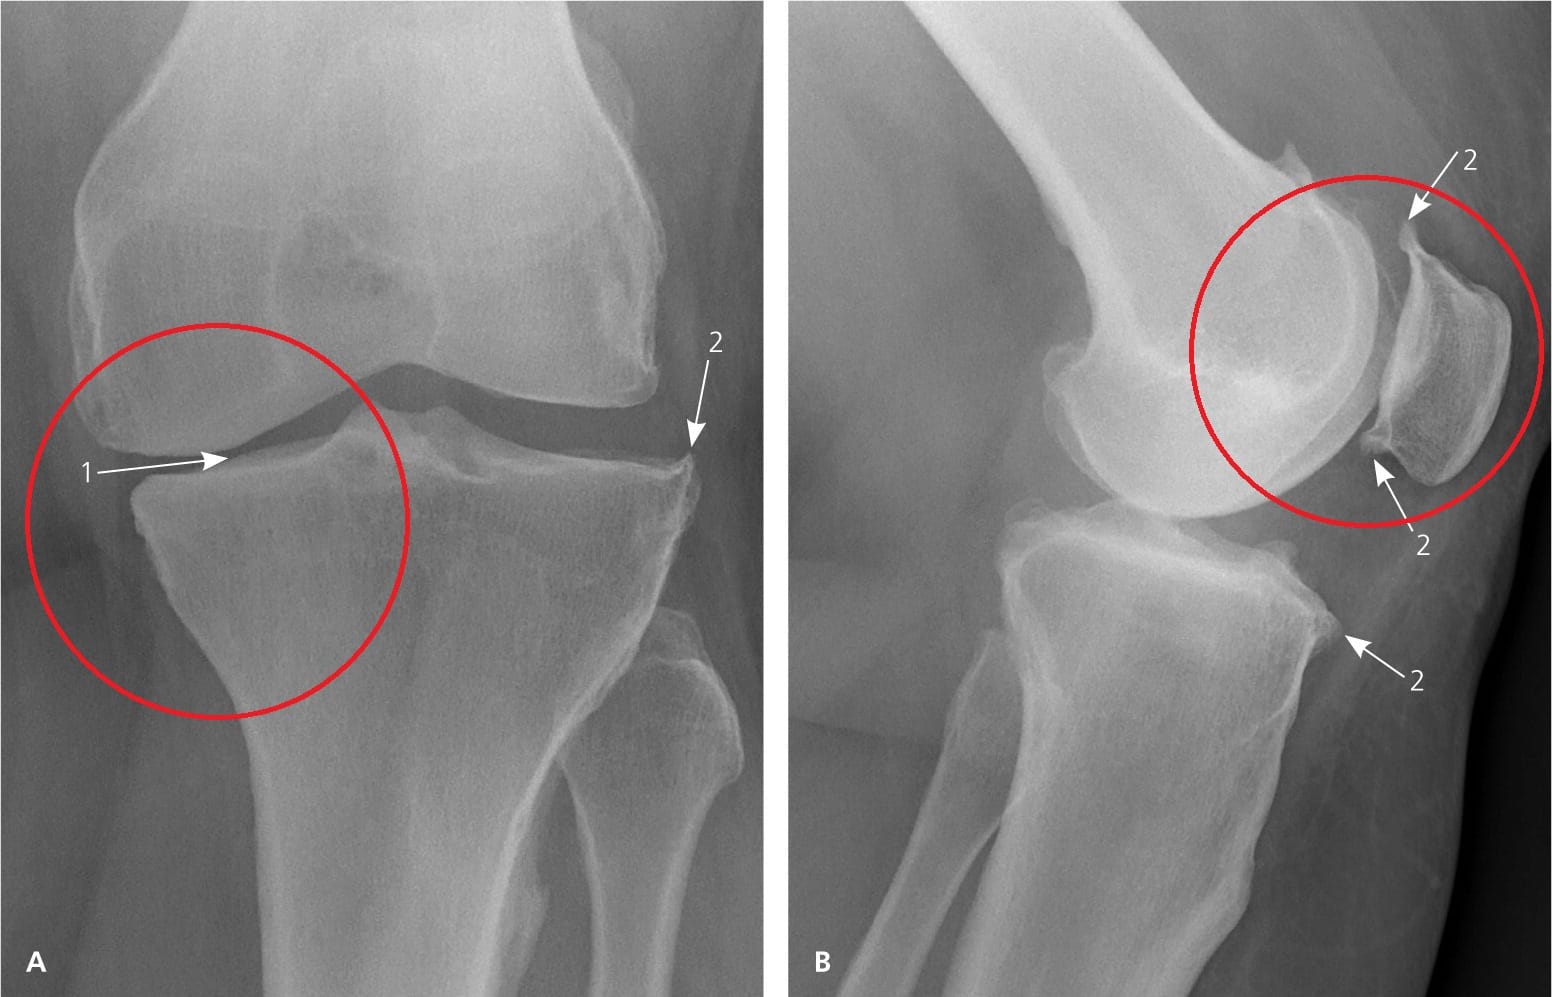

W końcu zostałam zbadany przez lekarza. Była starszy i myślałam, że na pewno ma doświadczenie. Przynajmniej taką miałam nadzieję... Bez zbędnych ceregieli zrobił mi pełne badanie, które obejmowało prześwietlenia rentgenowskie oraz badania krwi i moczu.

Na kolejnej wizycie dosłownie w ciągu kilku minut zdiagnozował u mnie wtórną chorobę zwyrodnieniową stawów z powikłaniami . Szczerze mówiąc, nie bardzo rozumiałam, co mówił. Wyjaśnił mi coś w niejasny sposób i odesłał do domu z listą tabletek.

Ale największą rzeczą, która mnie zszokowała, była przyczyna mojego bólu. „ To kwestia wieku ” – wyjaśnił mi lekarz. Ale w jakim wieku! Mam dopiero 53 lata i czuję się aktywną, pełną energii mamą moich 18-16-letnich dzieci, a nie starszą panią cierpiącą na chorobę zwyrodnieniową stawów.

Dzień 35: Miałam badania i prześwietlenia rentgenowskie. Żadnych objawów choroby zwyrodnieniowej stawów! Chrząstka w moich stawach była jak u 20-letniej dziewczyny. Lekarz stwierdził, że prawdopodobnie na poprzednim zdjęciu RTG wystąpiła wada, dlatego diagnoza choroby zwyrodnieniowej stawów była błędna.